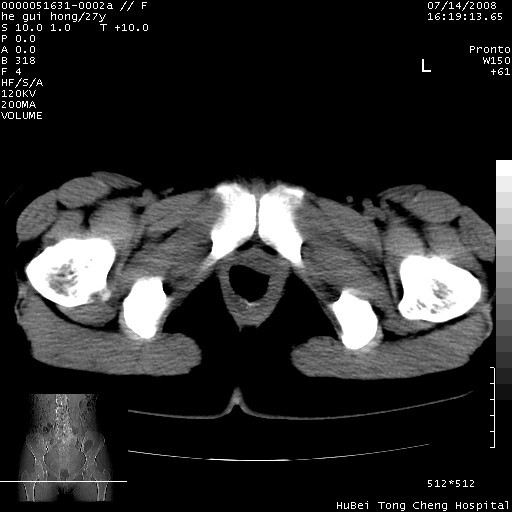

以下是引用杀毒软件在2008-7-20 8:03:00的发言:[br]支持双侧卵巢囊腺瘤可能性大!

以下是引用zjzjr在2008-7-20 13:36:00的发言:[br]双侧附件囊腺瘤可能性大!